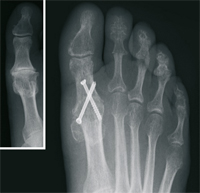

The Hallux valgus (balltoe)

Surgical correction without the presence of pain is not advisable from a purely cosmetic point of view. However, In case of pain in the big toe, the operative procedure is the only permanent therapeutic option.

After extensive examination, consideration of individual needs, as well as analysis of the X-ray images, the treatment is determined. Different internationally recognized surgical procedures are used. We use modern plates and titanium screws.

Claw Toe